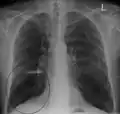

A chest X-ray is not useful to establish a diagnosis of COPD but it is of use in either excluding other conditions or including comorbidities such as pulmonary fibrosis and bronchiectasis. Characteristic signs of COPD on X-ray include hyperinflation (shown by a flattened diaphragm and an increased retrosternal air space) and lung hyperlucency.[5] A saber-sheath trachea may also be shown that is indicative of COPD.[110]

Chest X-ray demonstrating severe COPD, displaying small heart size in comparison to the lungs